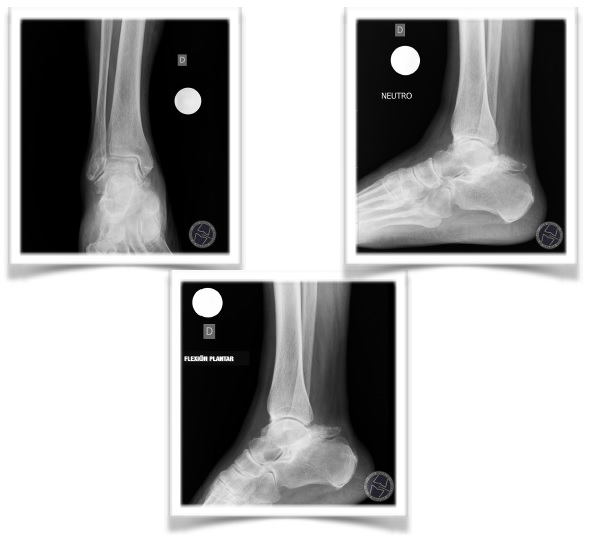

ESTUDIO POR IMAGEN: RX

Presencia de enorme OS TRIGONUM, osificación posterior a la articulación calcáneo-astragalina.

CONTROL RADIOGRÁFICO POSTOPERATORIO

En el control radiográfico postoperatorio se evidencia la completa resección del os

trigonum con la presencia del redón en la región profunda posterior del tobillo.